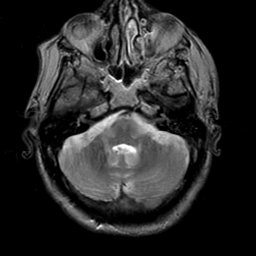

Meningioma, MR Study #2 -- Slice #3

[Home][Help][Clinical] Slice 3